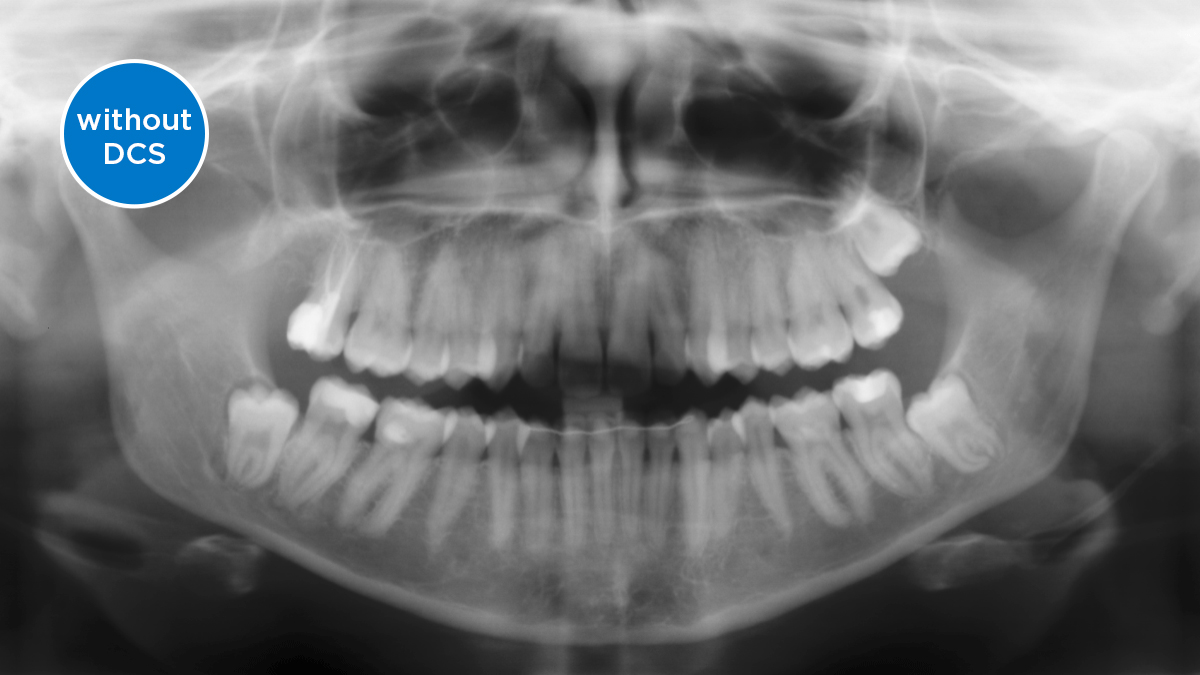

The Direct Conversion Sensor (DCS) has revolutionised the standard of panoramic imaging. X-rays are converted directly into electrical signals. Thus, there is no signal loss due to light conversion, as is the case with conventional systems. The result: images with a high level of sharpness and contrast – even at an extremely low radiation dose. For accurate diagnostic information to support targeted treatment.

The image below shows a panoramic X-ray without and with DCS technology. Using the arrow, drag the control across the image to see the difference the direct conversion sensor makes to the image quality and diagnostic possibilities.